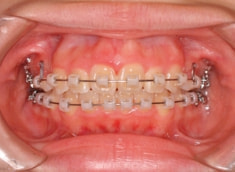

治療前

治療後(1年2ヶ月後)